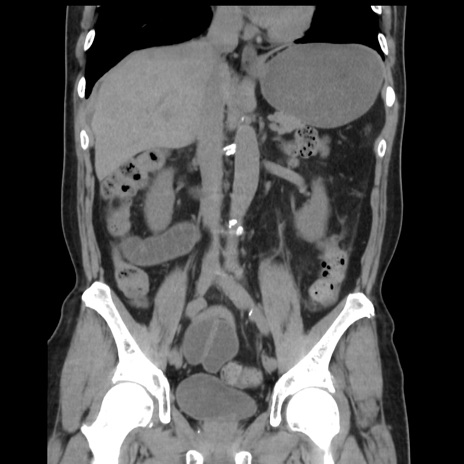

症例16(冠状断像)

【症例】 70歳代男性

【主訴】 腹痛、嘔吐

【現病歴】 約1ヶ月前より間欠的に腹痛と嘔吐あり、当院消化器内科を受診したところCTで多発する肝臓のLDAを指摘され、精査中であった。以降は消化器症状は安定していたが、2日前より嘔気と腹痛があり、同日より排便・排ガスが消失した。改善認めず、 本日、救急外来を受診した。

【既往歴】 大腸ポリープ切除後。

【身体所見】意識清明・会話良好、BT 36.3℃、BP 127/80mmHg、 P 80bpm、腹部:膨満あり、平坦・軟、上腹部正中および下腹部正中に圧痛あり、反跳痛なし、筋性防御なし。

【データ】WBC 7200、CRP 0.77